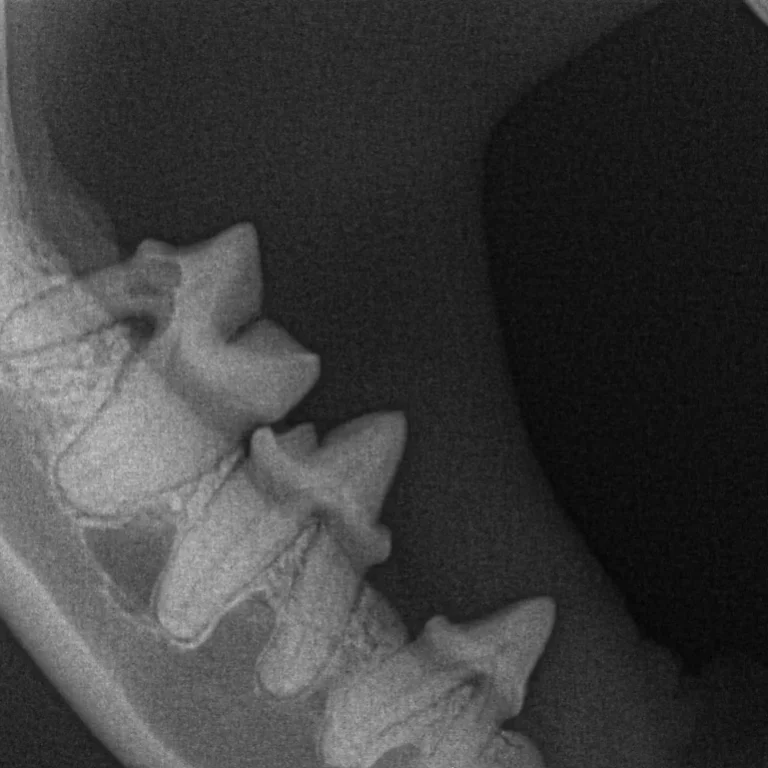

Digital Dental X-Ray

Dental radiographs are one of the most important diagnostic tools available to a veterinary dentist. They allow the internal anatomy of the teeth, the roots and the bone that surrounds the roots to be examined.